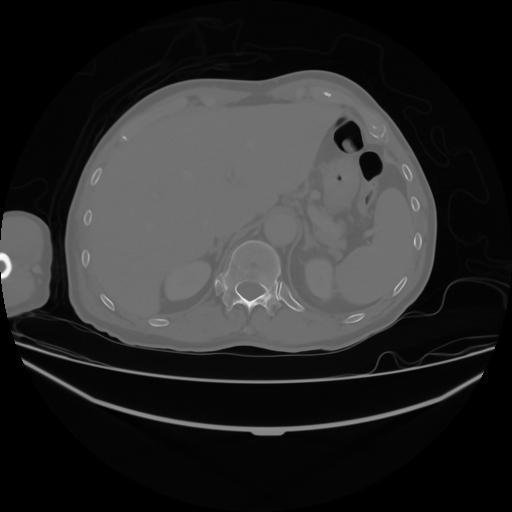

4 CUERPO,CE,Axial,3.0,CUERPO,,